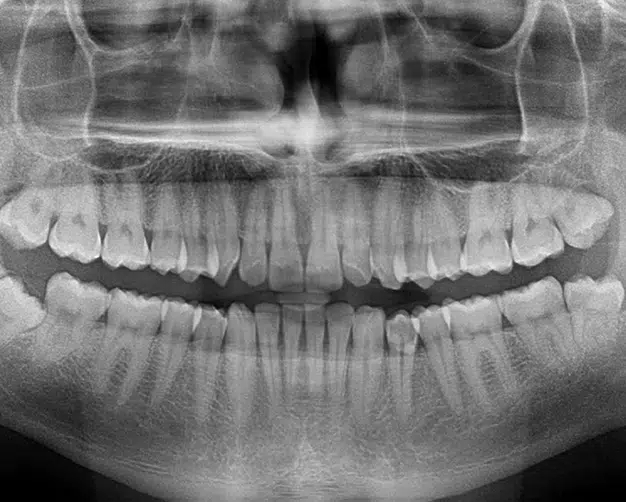

A panorex stands out as an impressive imaging tool, capable of revealing details and structures beyond the scope of a standard x-ray. During the procedure, you'll be seated with your chin resting on a small ledge, while the machine rotates around your head, capturing a complete 360-degree view of your teeth, head, sinuses, and bones.

This comprehensive view of your head's structure provides invaluable insights for the dentist. It enables us to detect potential issues and ensure optimal functionality. The panorex can identify various structural problems, infections, asymmetry, and more, offering a wealth of diagnostic information.